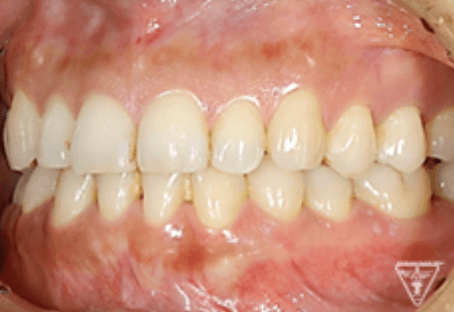

治療後